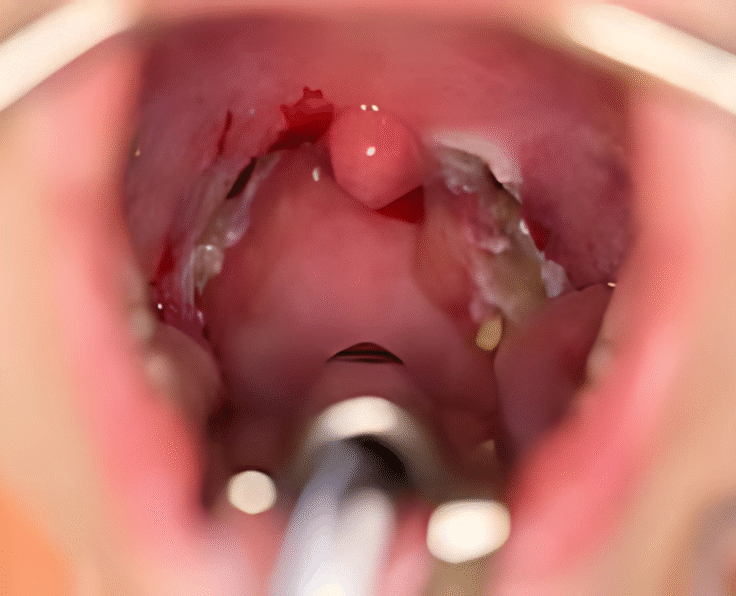

Practice Areas and Expertise

Combining precision medicine with aesthetic refinement to deliver care that’s both functional and transformative.